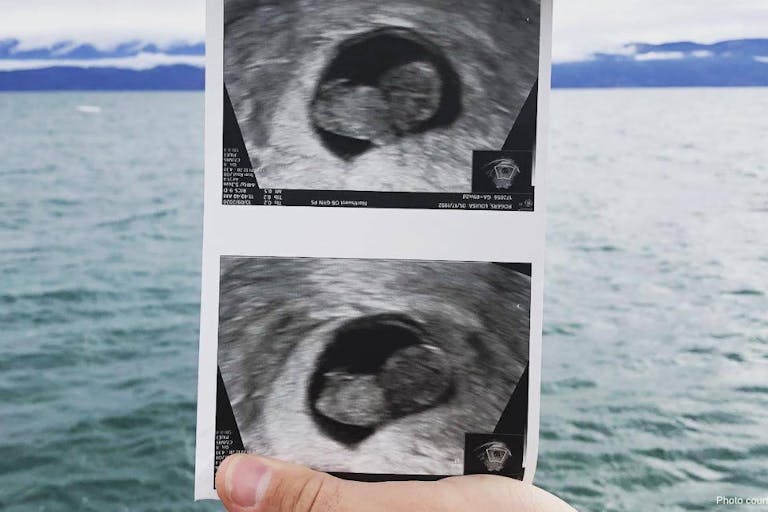

The technician located my baby, and everything was still. The baby was still. The room was still. “I don’t see a heartbeat,” she said quietly, after we had sat in silence for a minute. Justin was squeezing my hand tightly. I looked up at him, and he was weeping silently. She left us in the room alone, to wait for our midwife. We held each other and cried.

Saturday, October 10, 2020 – 2:00 in the morning. Our baby, perfectly formed with fingers and toes, lay in a box in Justin’s hands. Pain, grief, wonder. Together, we looked at that perfect baby, in complete awe and adoration, and heartbreak.

I didn’t pass the tissue. I delivered my baby. My tiny, perfect baby.

You may be wondering why I wrote this and why I am sharing this. One of the reasons I didn’t shout my pregnancy from the rooftops is because I knew that if I did miscarry, I would want to grieve in private. Or so I thought. But that is not how I feel at all. After seeing my baby – my perfect, perfect baby – all I want to do is show everyone I see a picture of her. I want to acknowledge her. I want to shout from the rooftop that she existed and was part of me and was a person and was our baby. I want to grieve openly and honestly.

I share the picture of my baby with you today, because I want you to see how perfect and beautiful she is. She is not “tissue.” She is a baby. And whenever I think of her, the grief and wonder I feel will be forever intertwined.